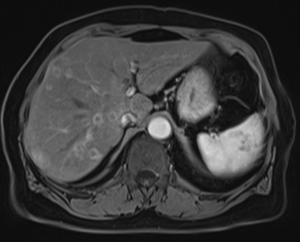

МР-диагностика образований печени (с использованием гепатоспецифичного контрастного препарата)